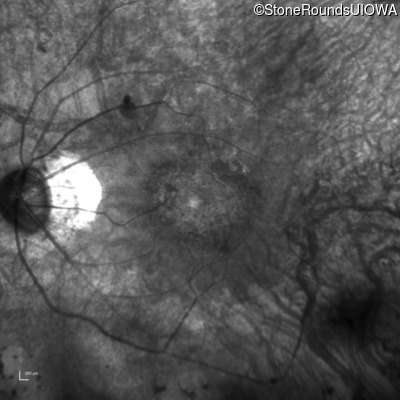

Infrared Fundus Photograph - Right - 20/20

Exemplar